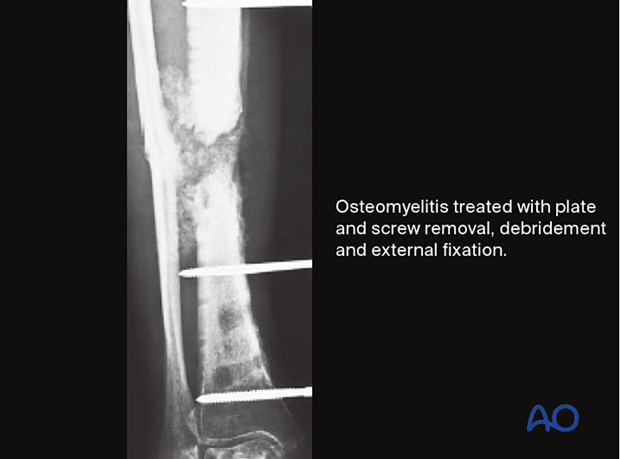

This patient had an acute fracture, necessitating internal fixation. However, a late infection occurred. X-rays and subsequent debridement revealed an ununited fracture with minimal callus formation. Intercalary necrotic bone was debrided. The fracture was stabilized with an external fixator.

Appropriate antibiotics were administered. Bone graft was then placed in the fracture defect and between the tibia and fibula above and below the fracture. This combination of treatments improved both the biology and stability of the atrophic nonunion. Delayed healing occurred with a satisfactory outcome.